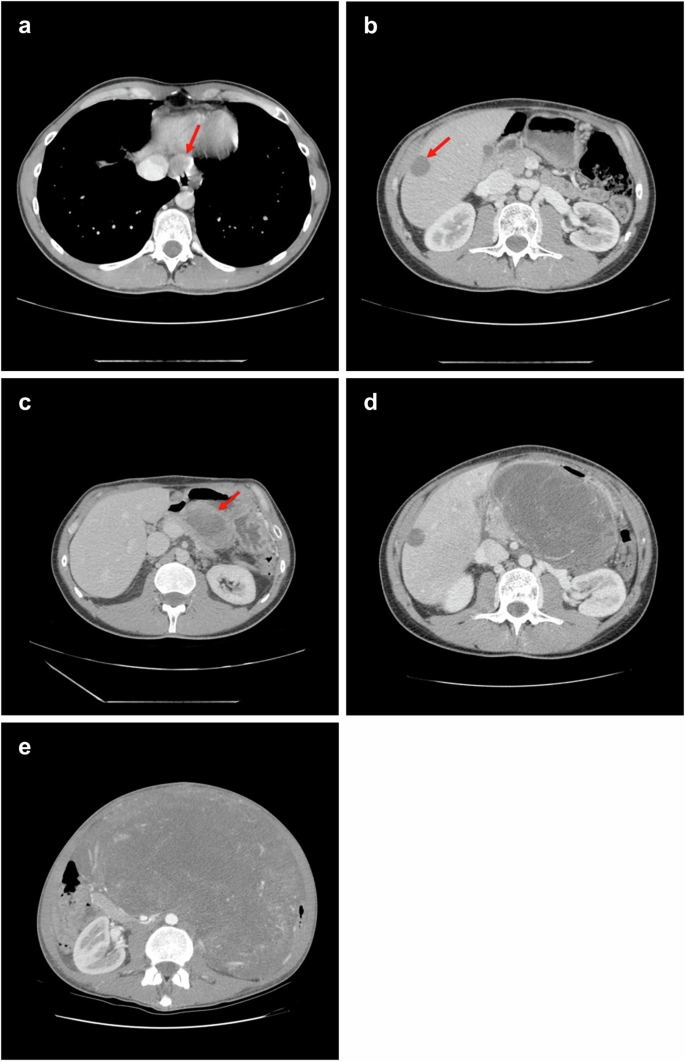

Post-surgical imaging confirmed disease-free status. Considering the advanced status of the disease, adjuvant imatinib (400 mg/day) was initiated (February 2015) but discontinued after 18 months at the patient’s request. Clinical follow-up was maintained thereafter. In June 2017 (31 months post-diagnosis), the patient presented with epigastric pain and a palpable mass; imaging revealed a 26 mm hepatic lesion and multiple epigastric nodules consistent with neoplastic recurrence. Imatinib (400 mg/day) was restarted, leading to marked regression of lesions (Fig. 2a, b). In February 2018 (39 months post-diagnosis), PET/CT (Positron Emission Tomography/Computed Tomography) showed diffuse peritoneal “sarcomatosis”, including a gastric mass, and peritoneal and periesophageal nodules (Fig. 2c). Imatinib was escalated (800 mg/day) but disease progressed (Fig. 2d). Debulking surgery was performed (April 2018).

a, b Follow-up CT scan from September 2017 shows a partial response to imatinib, with reduced size of periesophageal and hepatic lesions (red arrows). c By February 2018, CT imaging reveals disease progression, with new intra-abdominal lesions, including an 8 cm perigastric mass with central necrosis (red arrow). d Following imatinib dose escalation, further progression is observed, including enlargement of the perigastric mass. e Imaging obtained at the late-stage of disease showing a large tumor mass occupying most of the abdominal cavity.

Pathological examination revealed an atypical undifferentiated spindle and ovoid cell morphology set in a myxoid stroma. Diffuse areas of necrosis were present and mitotic index was elevated, including atypical forms (Fig. 1g–i). The tumor was CD117 negative but showed strong, albeit multifocal, DOG1 positivity (Fig. 1j, k). Molecular analysis of tumor DNA revealed the KIT exon 11 mutation (pW557_V559delinsF) originally detected in the primary lesion (Fig. 1l). No canonical KIT resistance mutation was identified. The combination of clinical history, immunophenotype, and molecular data, despite the absence of classic GIST morphology, was consistent with the diagnosis of relapse of GIST that had undergone dedifferentiation. Sunitinib (37.5 mg/day) was initiated but the patient experienced rapid disease progression and died shortly after (June 2018) (Fig. 2e).